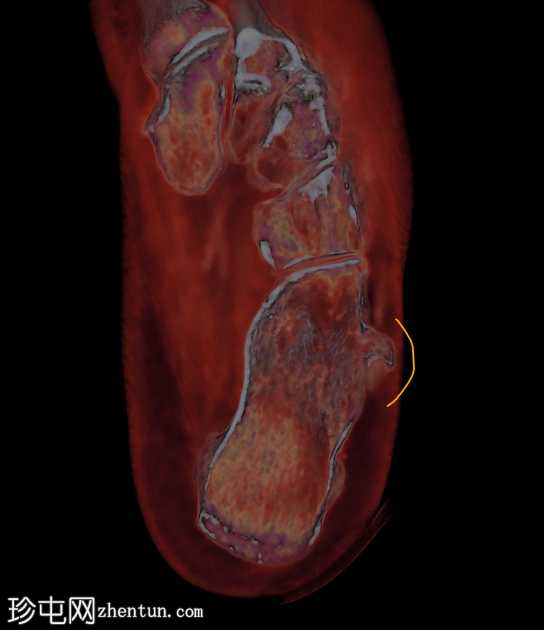

跟骨外侧

疼痛

。

年龄:65岁

性别:女

腓骨结节解剖图(带注释)

病例讨论